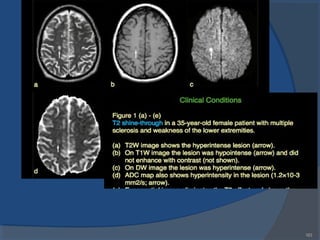

In certain cases, alargeareaof demyelination, for example, alesion, may

havevery high signal on theT2-weighted imagewhileitsdiffusion isnot

very different from that of normal tissue. Becausethemagnitudeof

diffusion issimilar to normal brain, thesignal intensity of thelesion will b

attenuated by thediffusion-sensitizing gradientsto adegreesimilar to

normal brain. Nonetheless, thelesion will demonstratevery high signal on

thediffusion-weighted image. Whereasit might lo o k similar to infarction,

thehigh signal doesnot represent adeclinein diffusion; even with the

reduction in signal dueto diffusion, signal on thediffusion-weighted imag

isstill high becausetheinitial signal on theT2-weighted imageisso high.

Thispitfall iscalled T2 shine-thro ugh

T2 shine-through

180

If weplot signal intensity from an imagewithout diffusion

sensitization and that from adiffusion-sensitized image, theslopeof the

resultant linewill approximatetheapparent diffusion coefficient (ADC).

Wethushaveaquantitativemeasureof diffusion. Becausethisapproach

actually measuresthedegreeof signal lossdueto thediffusion- sensitizing

gradient, it may solvetheproblem of T2 shine-through.

Whereasalesion with very high signal on theb = 0 imagemight show

high signal on thediffusion-weighted image, measuring theADC will

show avaluesimilar to normal tissue.

ADC

Diffusion images. When diffusion-sensitizing gradientsareadded to

theTI-weighted EPI image(left), adiffusion-sensitized or diffusion-weighted image

(DWI) (center) results. Themagnitudeof diffusion can bequantified and displayed

asan ADC image, often called an ADC map (right).

182

Acutestrokeshown by diffusion imaging. High signal in thediffusion weighted image

(DWI) (black arrow) isdueto diminished diffusion and manifests

aslowADC in thequantitativeADC image(whitearrow).